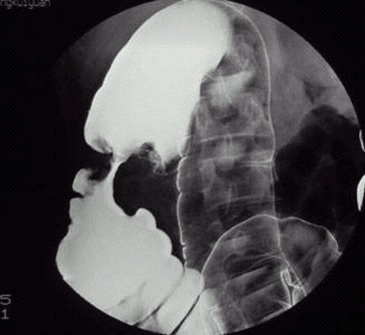

05卷-3.病史:女性,52歲,觸及腹部包塊3周。診斷(本題滿(mǎn)分2.00分)

本題答案:B

題目解析:【該題針對(duì)“造影-結(jié)腸癌”知識(shí)點(diǎn)進(jìn)行考核】